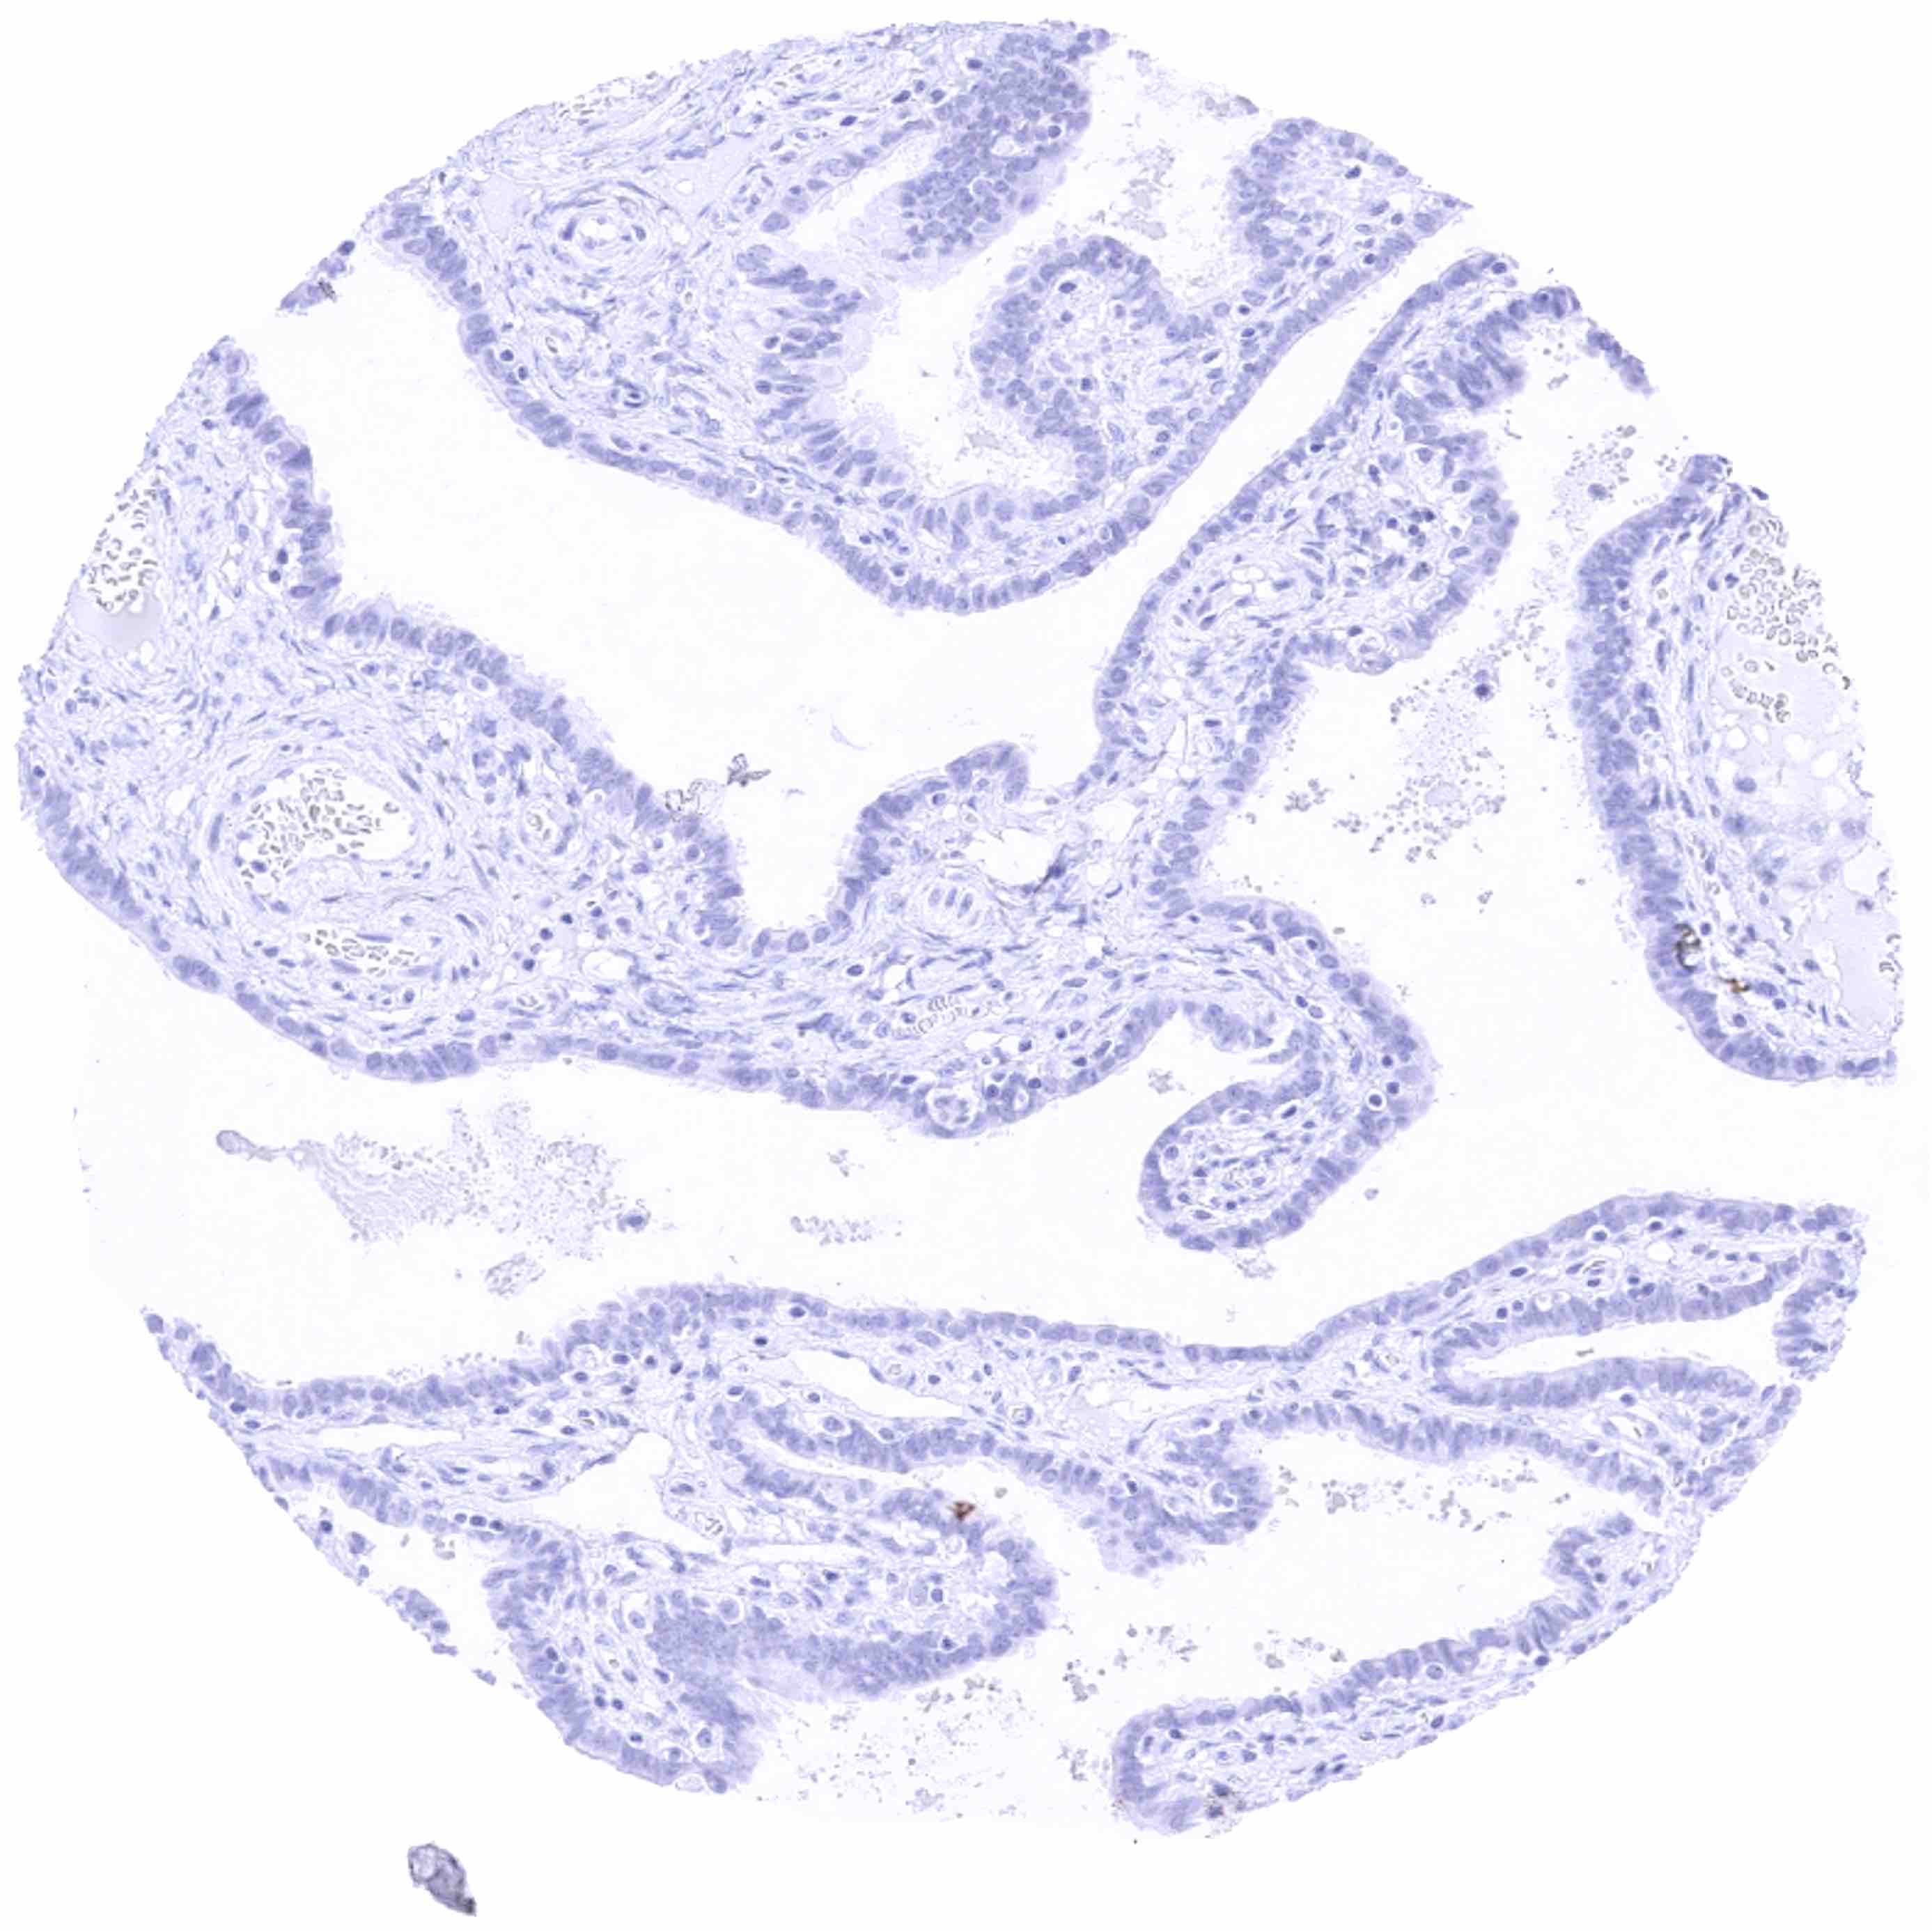

Fallopian tube, mucosa